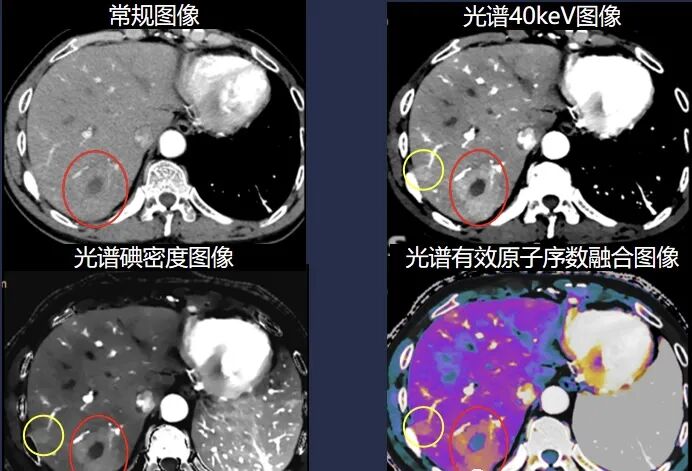

肿瘤诊疗一体化,让肿瘤无处遁形

皓克CT的多参数低keV、有效原子序数、碘含量、虚拟平扫等多种参数可对全身各部位肿瘤进行多角度分析,突破传统CT的等密度病灶局限,超早期即可发现肿瘤病变,并可对其进行准确定量、定性分析,辅助肿瘤的准确分期、分级,协助临床制定治疗方案。